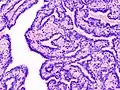

Histopathology of intraductal papilloma of the breast by excisional biopsy. Hematoxylin and eosin stain.- Histopathology of intraductal papilloma of the breast by excisional biopsy. Immunostaining for alpha-smooth muscle actin.